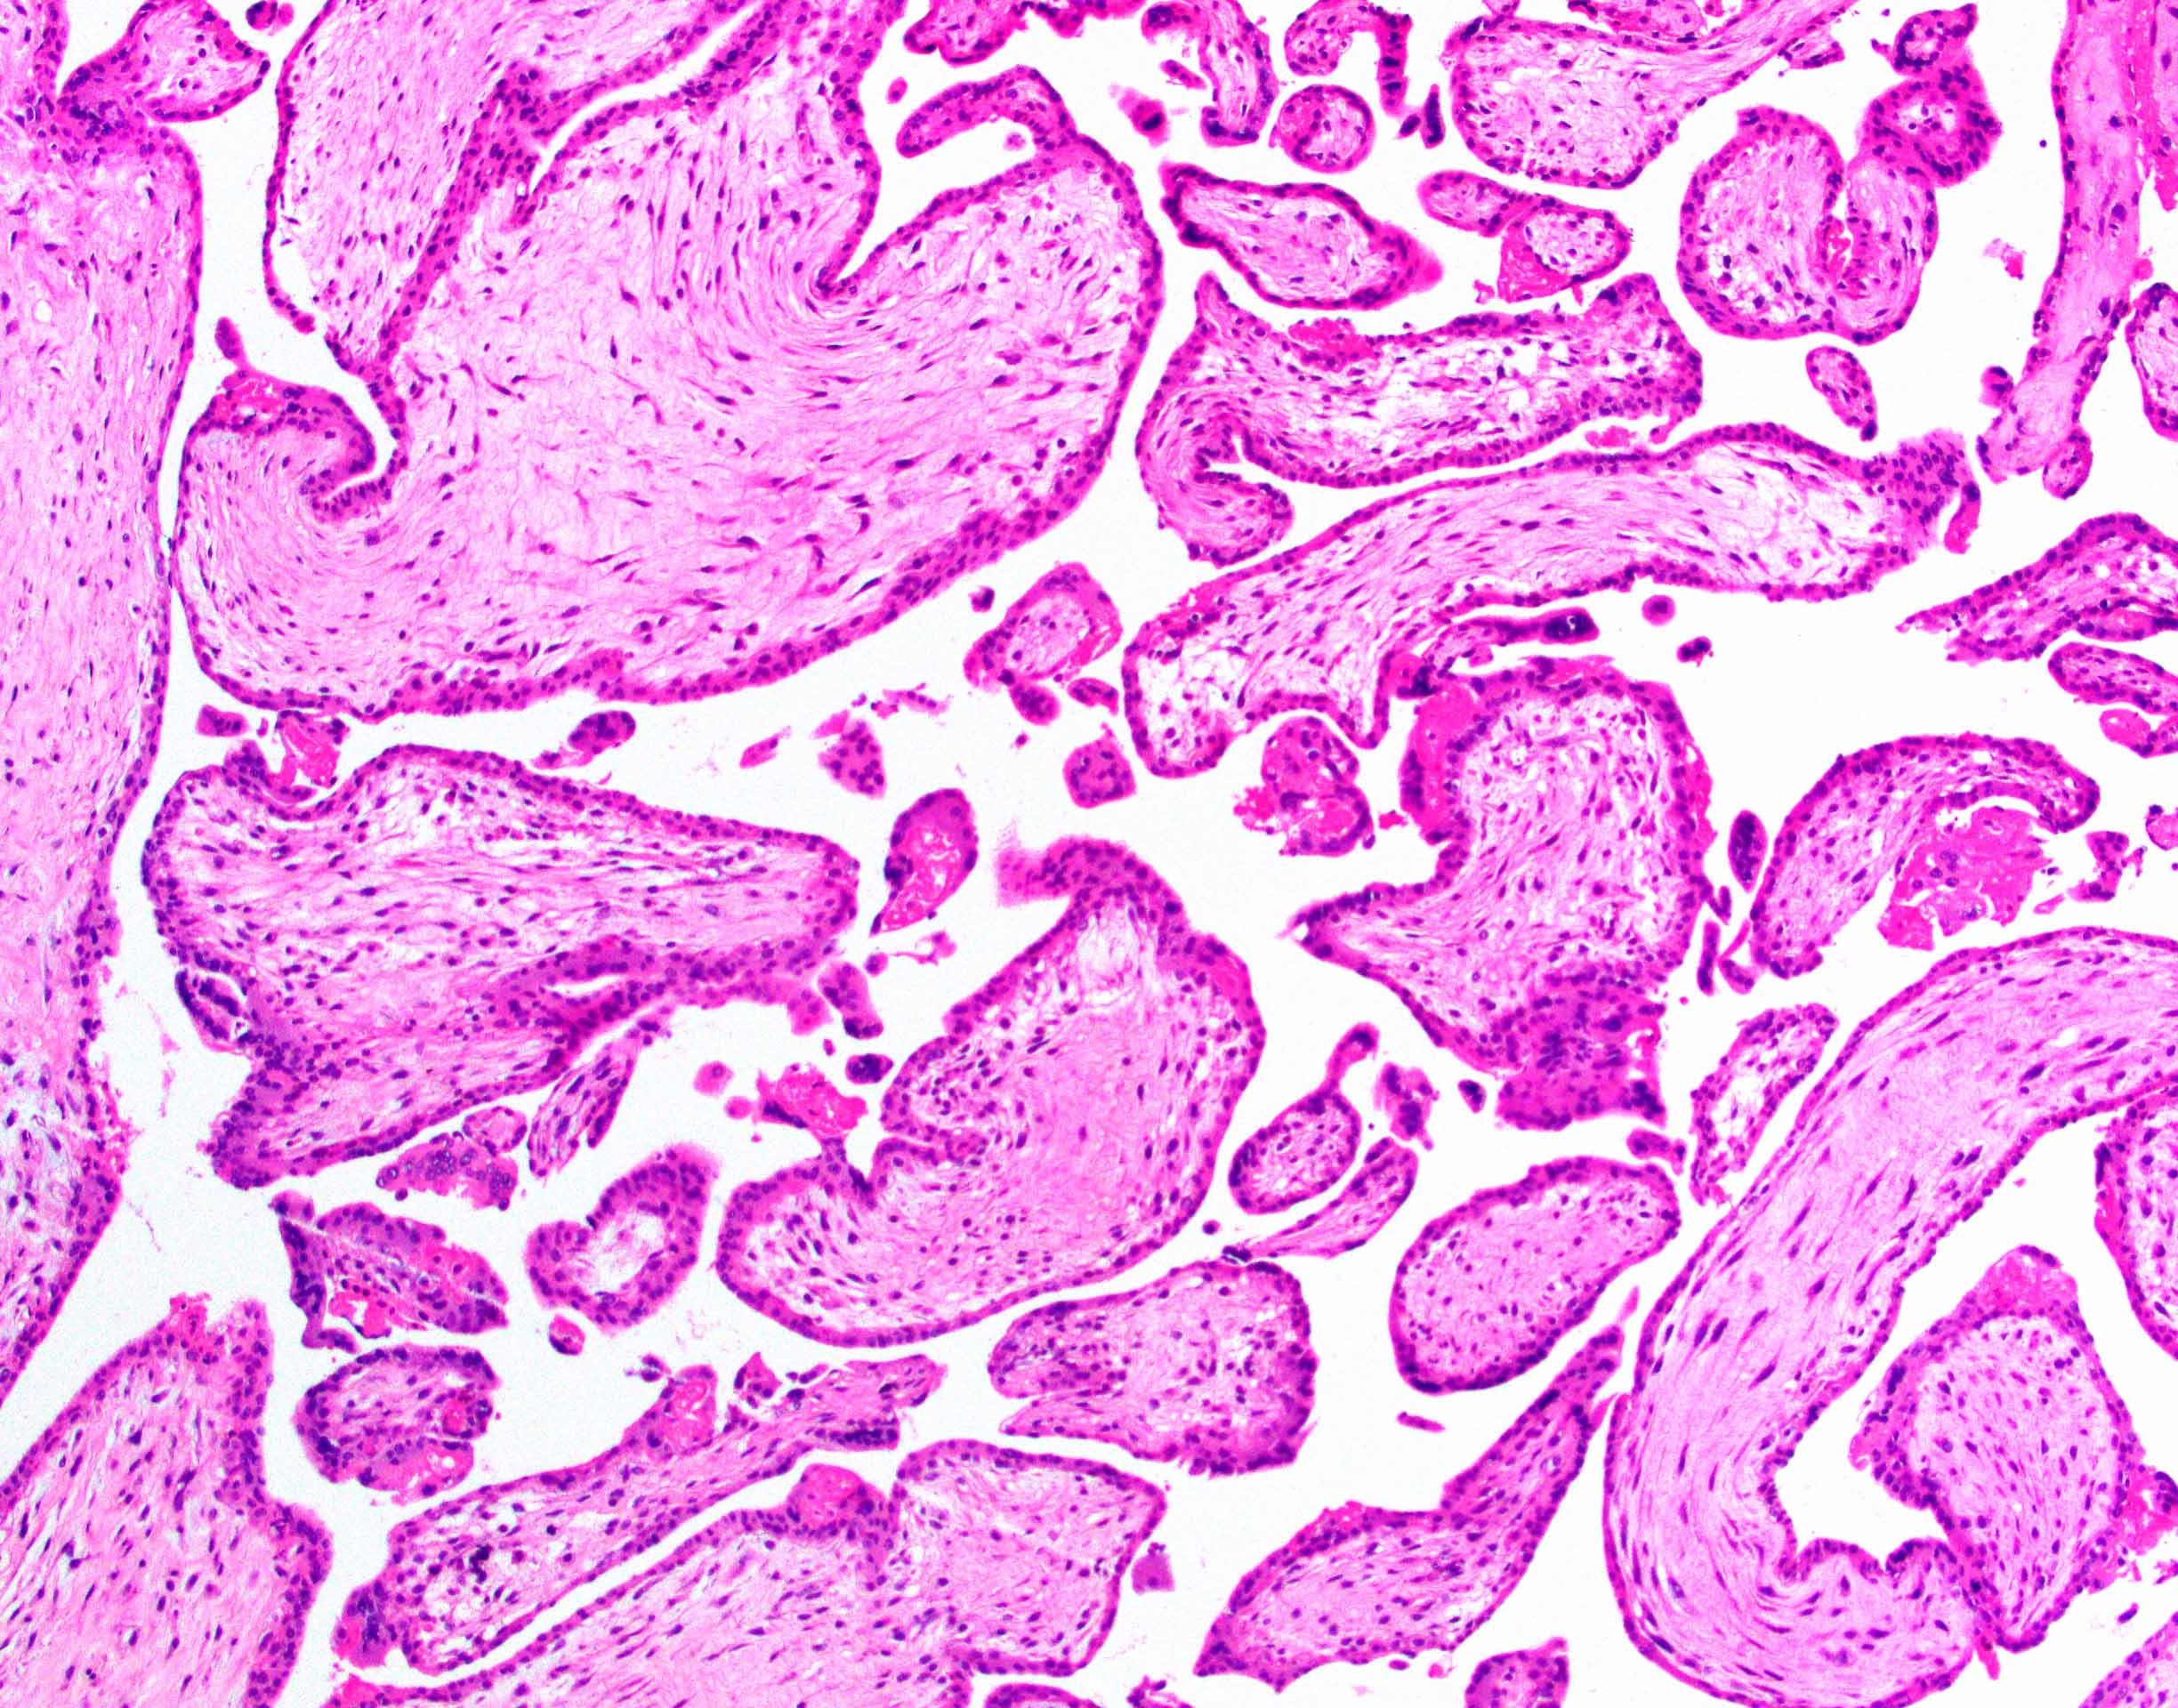

Microscopic (histologic) description

- Removed or passed products of conception may contain:

- Early first trimester chorionic sac (< 8 weeks): thin chorion and scant villi that are sparsely or nonvascularized

- Villous trophoblast is bilayered (mononuclear cytotrophoblast inner layer and multinucleated syncytiotrophoblast outer later) and circumferential with occasional polarized trophoblast protrusions

- Mid first trimester chorionic sac (8 - 10 weeks): may exhibit recognizable amnion, early stromal collagenization of chorion and proximal villi and increased volume of distal villi with distinct capillaries

- Later first trimester chorionic sac (> 10 weeks): may exhibit loose fusion of amnion and chorion, a more collagenized chorion and stem villi, more distinct walls of fetal vessels and numerous villi with increasing demarcation between proximal and distal branches

- Spectrum of villous changes in immature chorionic villi following embryonic death (Placenta 2005;26:114):

- Cellular debris within villous vessels - earliest change

- Villous edema with myxoid stromal degeneration - may be confused with molar gestation

- Collagenized avascular villi (villous sclerosis / fibrosis)

- Villous edema and sclerosis / fibrosis often coexist

- Other findings: prominent perivillous fibrin with prolonged retention or in medical abortions, otherwise pathologic

- Spectrum of villous morphology in nonmolar abnormal karyotype (Hum Pathol 1995;26:201):

- Dysmorphic appearance (lacks sensitivity and specificity): highly irregular villous shapes / outlines, occasional trophoblastic inclusions

Microscopic (histologic) images

Contributed by Chrystalle Katte Carreon, M.D. and Drucilla J. Roberts, M.D.